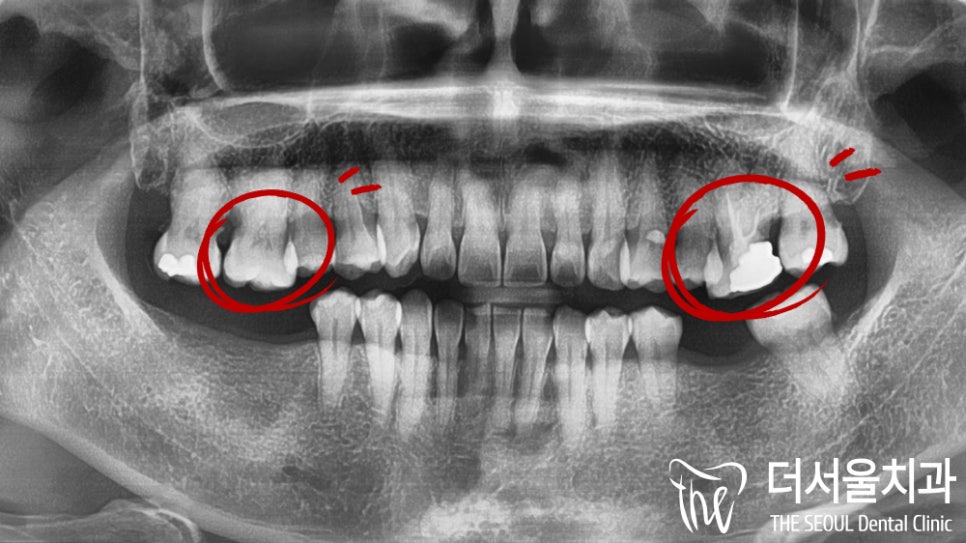

우선 환자의 구강 내를 살펴보니

줄어들어 있는 잇몸 폭을 볼 수 있는데요.

이가 빠진 채로 오랜 시간 생활을 하셨던터라

치조골 소실이 일어나게 된 것입니다.

문제는 여기서 끝이 아니였습니다.

상악 양쪽 어금니 부근에

심한 충치가 생겨 있음을 확인할 수 있었는데요.

치근 부근까지 심하게 진행되어

이곳도 함께 치료를 진행해야겠네요.